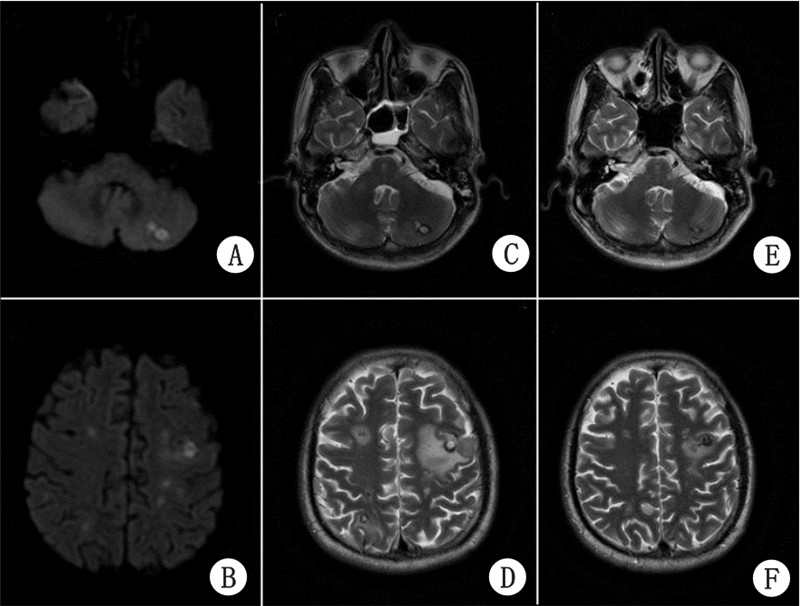

检查资料:全身皮肤、黏膜未见感染病灶及破损。血培养已进行(2013-05-05),结果等待中。头MRI(2013-05-06):双侧脑额顶枕叶皮髓质交界处及左侧小脑半球多发散在异常信号灶、感染性病灶,与转移瘤待鉴别,少量蛛网膜下腔出血(图 3A、3B)。头MRA:脑动脉MRA未见明显异常。

| A、B:头MRI DWI象(2013-05-06):双侧脑额顶枕叶皮髓质交界处及左侧小脑半球多发散在异常信号灶,感染性病灶,与转移瘤待鉴别;C、D:头MRI T2加权象(2013-6-4):双侧脑额顶枕叶皮髓质交界处多发异常信号灶,边界清楚,周围水肿,左侧小脑半球异常信号灶,考虑脑脓肿;E、F:头MRI T2加权象(2013-6-24):病灶较C、D明显缩小,周围水肿减轻 图 3 患者头MRI结果 |

检查资料:血培养(48 h后)结果为金黄色葡萄球菌,多药敏感。头MRI(2013-06-04):双侧脑额顶枕叶皮髓质交界处多发异常信号灶,边界清楚,周围水肿,左侧小脑半球异常信号灶,考虑脑脓肿可能(图 3C、3D)。

IE指南强调,对于已有瓣膜病变如二尖瓣脱垂、严重瓣膜钙化者及赘生物<2 mm或无赘生物者,超声诊断较难[4]。然而这些赘生物确实存在,且软而脆,易脱落形成脓毒栓子。Duval等[5]认为,对于怀疑IE的患者,无论是否存在神经系统并发症表现,都应行头MRI检查,DWI图象对鉴别播散性感染灶较敏感,早期阳性发现对IE的诊断和颅内感染的治疗均有积极意义。本例经胸和经食道超声均未发现赘生物,但是血培养阳性和头MRI强烈支持。

患者初始罗氏芬2 g每日一次静点,第3天血培养结果回报革兰阳性球菌,联合万古霉素0.5 g每日三次静点。1周后,神志转清,言语迟缓,左侧额纹、鼻唇沟消失,伸舌左偏,颈抵抗阴性,右侧肢体肌力2级,左侧肢体肌力5级,双侧Babinski征阳性。4周后,言语流利,双侧额纹、鼻唇沟对称,伸舌居中,双侧肢体肌力5级。6周后,血象正常,PCT<0.05 ng/mL(重症感染患者PCT<0.5 ng/mL被认为是停止抗生素指征之一[10]),停用万古霉素,病情无反复。复查头MRI(2013-06-24),病灶较6月4日缩小,周围水肿减轻(图 3E、3F)。8周后,转院继续治疗,由于并发颅内感染,建议抗感染治疗3~6个月。